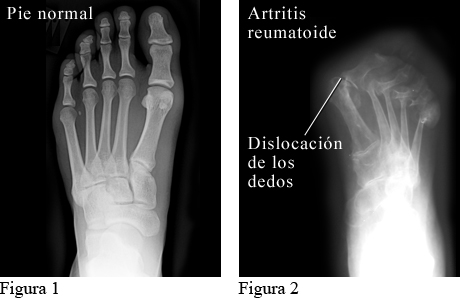

Radiografía de la artritis reumatoide en los pies